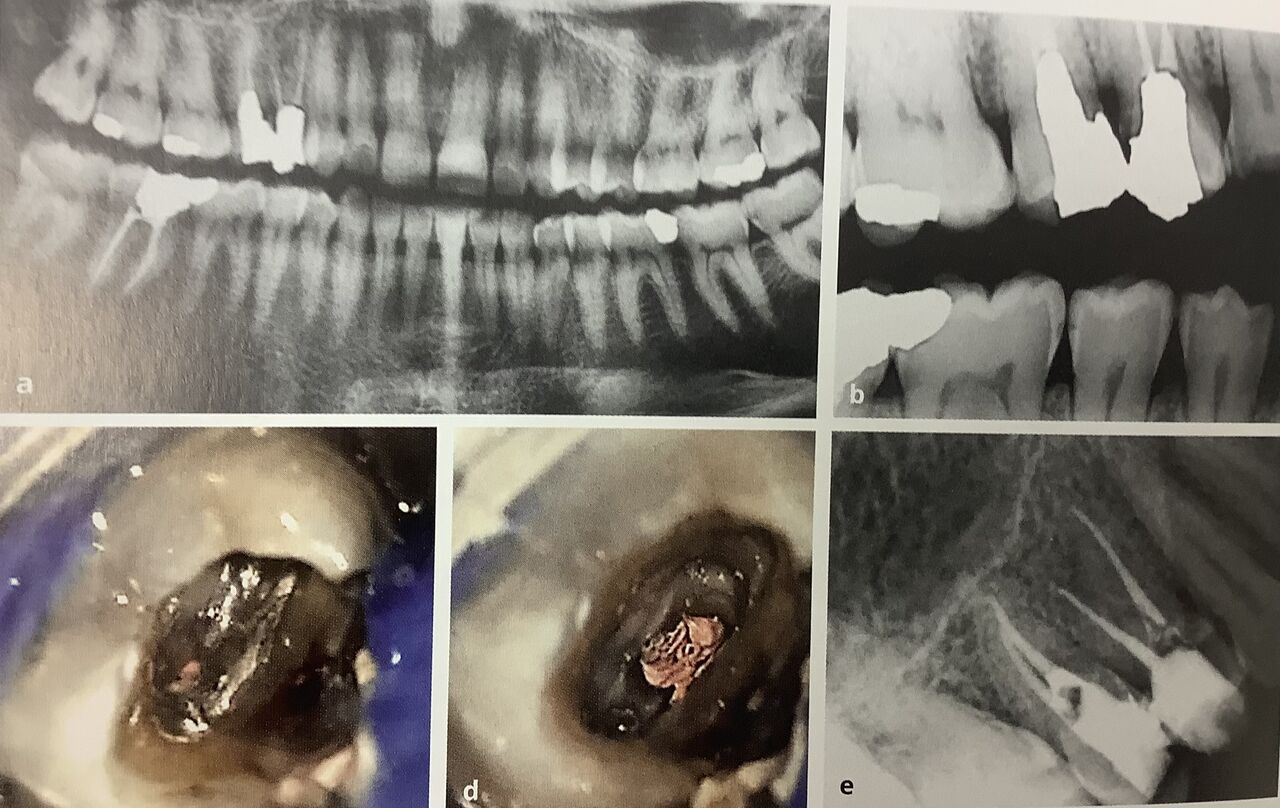

上が治療前

顕微鏡で覗いた神経の入り口部分です。

オレンジ色のが古いガッタパーチャ、クスリです。

左でキラキラ光って見えてるのが、

残ったポストの金属です。

右下がその治療後です。

同じ2本の神経でも、

別々に分かれているのと、

V字に出口でくっ付いてるのですね。